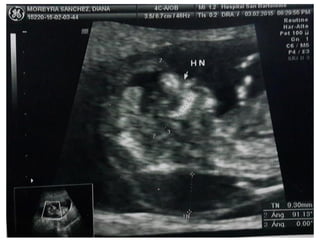

HUESO NASAL

• Corte sagital medio. Magnificación de la imagen.

• En esta posición tenemos que ver tres líneas :

– 1-2: 2 líneas paralelas más cercanas a la frente del feto,

la más externa corresponde a la piel y la más interna al

hueso nasal (de más grosor y ecogenicidad)

– 3: Otra línea a un nivel más alto que la piel que es la

punta de la nariz.

HUESO NASAL • Cortesagital medio. Magnificación de la imagen. • En esta posición tenemos que ver tres líneas : – 1-2: 2 líneas paralelas más cercanas a la frente del feto, la más externa corresponde a la piel y la más interna al hueso nasal (de más grosor y ecogenicidad) – 3: Otra línea a un nivel más alto que la piel que es la punta de la nariz.